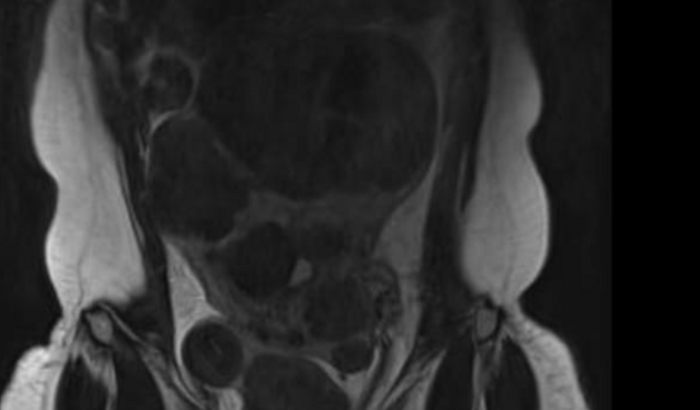

Tenho mais de 20 miomas, endometriose profunda, cisto nos 2 ovarios e o meu utero tem uma aderência com o intestino, alguns miomas estão gigantes .

Os miomas estão imprenssando o meu rim direito e estou correndo risco de perder o rim,